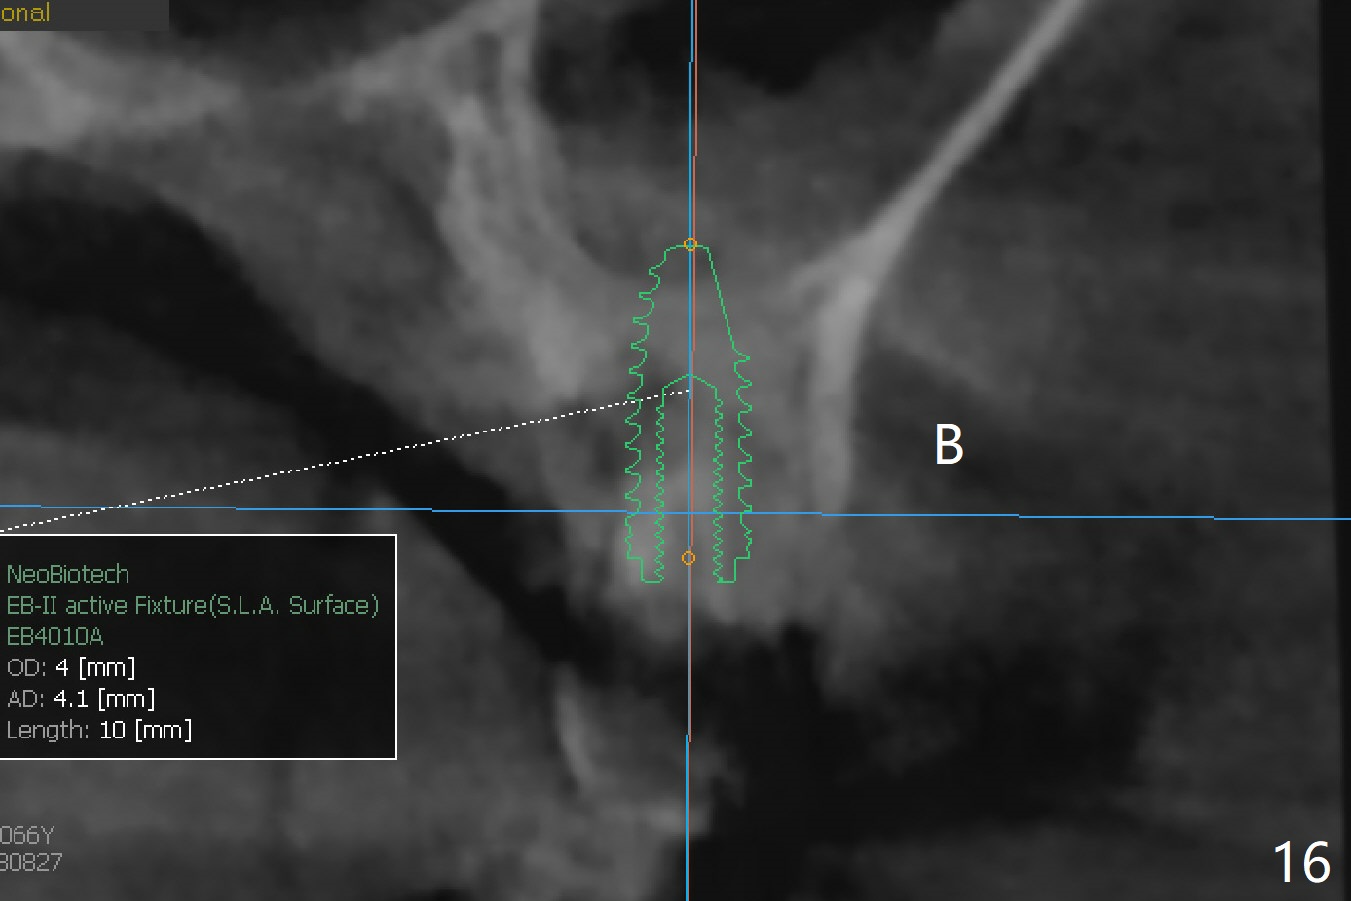

There is more bone apical to the residual root at #13 (Fig.1 red line). An immediate implant along the long axis of the root can be longer, 11.5 mm, favorable for primary stability (Fig.2 (CT taken immediately preop)). The initial trajectory is not ideal (Fig.3). When the pointed/Lindamann bur is removed (Fig.4), effort is made to move the apical end of the osteotomy distal (Fig.5 red arrow) by removing the apical bone (red dashed line). Following sequential osteotomy, a 4x10 mm dummy implant is placed with the trajectory remaining not so ideal (Fig.6,7). As the dummy implant is removed (Fig.8), a new osteotomy is established distal to the existing one (Fig.9). Subsequent drills gradually shift into the original osteotomy (Fig.10 red arrow). When the same dimension dummy implant returns, the trajectory improves with decreased stability (Fig.11). It seems reasonable to place a larger implant without further osteotomy. After placing PRF membrane and Vanilla graft for sinus lift (Fig.13 *), a 4.5x10 mm definitive implant is placed with loss of control in the trajectory (Fig.12,13).

When the initial osteotomy is off substantially (Fig.4), an osteotomy should be established de novo and as early as possible (Fig.14) so that subsequent osteotomy will not relapse to a great extent. More ideally, the initial osteotomy should be planned correctly (Fig.15,16) with sacrifice of the bone height. Nearly 1 month postop, the 4.5x5.5(5) cementation abutment is loose. When it is removed, the patient feels pain from the implant. A 5.5x6 mm healing abutment is placed instead. The implant osteointegrates with trabecular pattern in the sinus 9 months postop (Fig.20 *). The gingiva around the crown at #13 is healthy 1 year 4 months post cementation (Fig.18). Check the distal surface of #13 for bone loss if the tooth #14 is to be extracted.